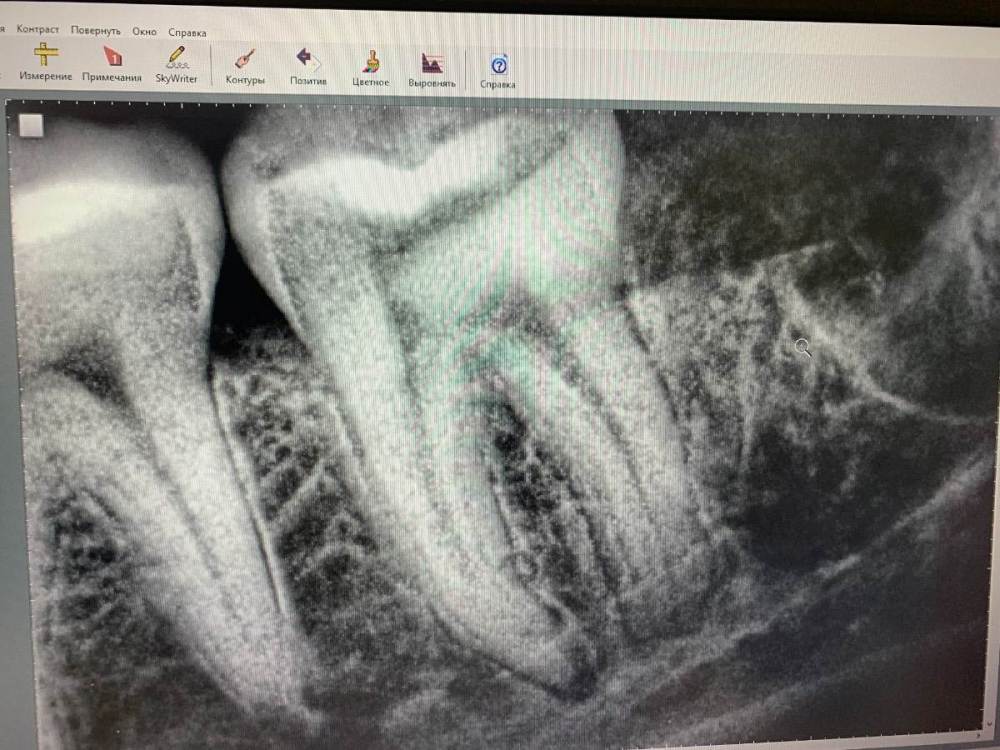

Nadezda79 Опубликовано 11 апреля, 2022 Автор Поделиться Опубликовано 11 апреля, 2022 Здравствуйте! С момента удаления прошел месяц. Полторы недели я ходила на промывку лунки и перевязки. Но пару дней назад возобновились болевые ощущения (не сильные) преимущественно под вечер в области лунки и семерки, челюсти под ней. Так же до сих пор присутствует онемение части щеки. Уважаемые врачи, что вы можете сказать по поводу снимка? Ссылка на комментарий

Irouil Опубликовано 11 апреля, 2022 Поделиться Опубликовано 11 апреля, 2022 Снимок не полный, но в той части лунки, которую он охватывает, ничего настораживающего не вижу Ссылка на комментарий

red_butler Опубликовано 12 апреля, 2022 Поделиться Опубликовано 12 апреля, 2022 Я бы проверил 7 зуб на витальность, по снимку на периодонтит похоже Ссылка на комментарий